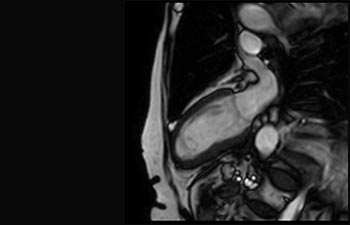

Mayor fiabilidad diagnóstica en neurooncología